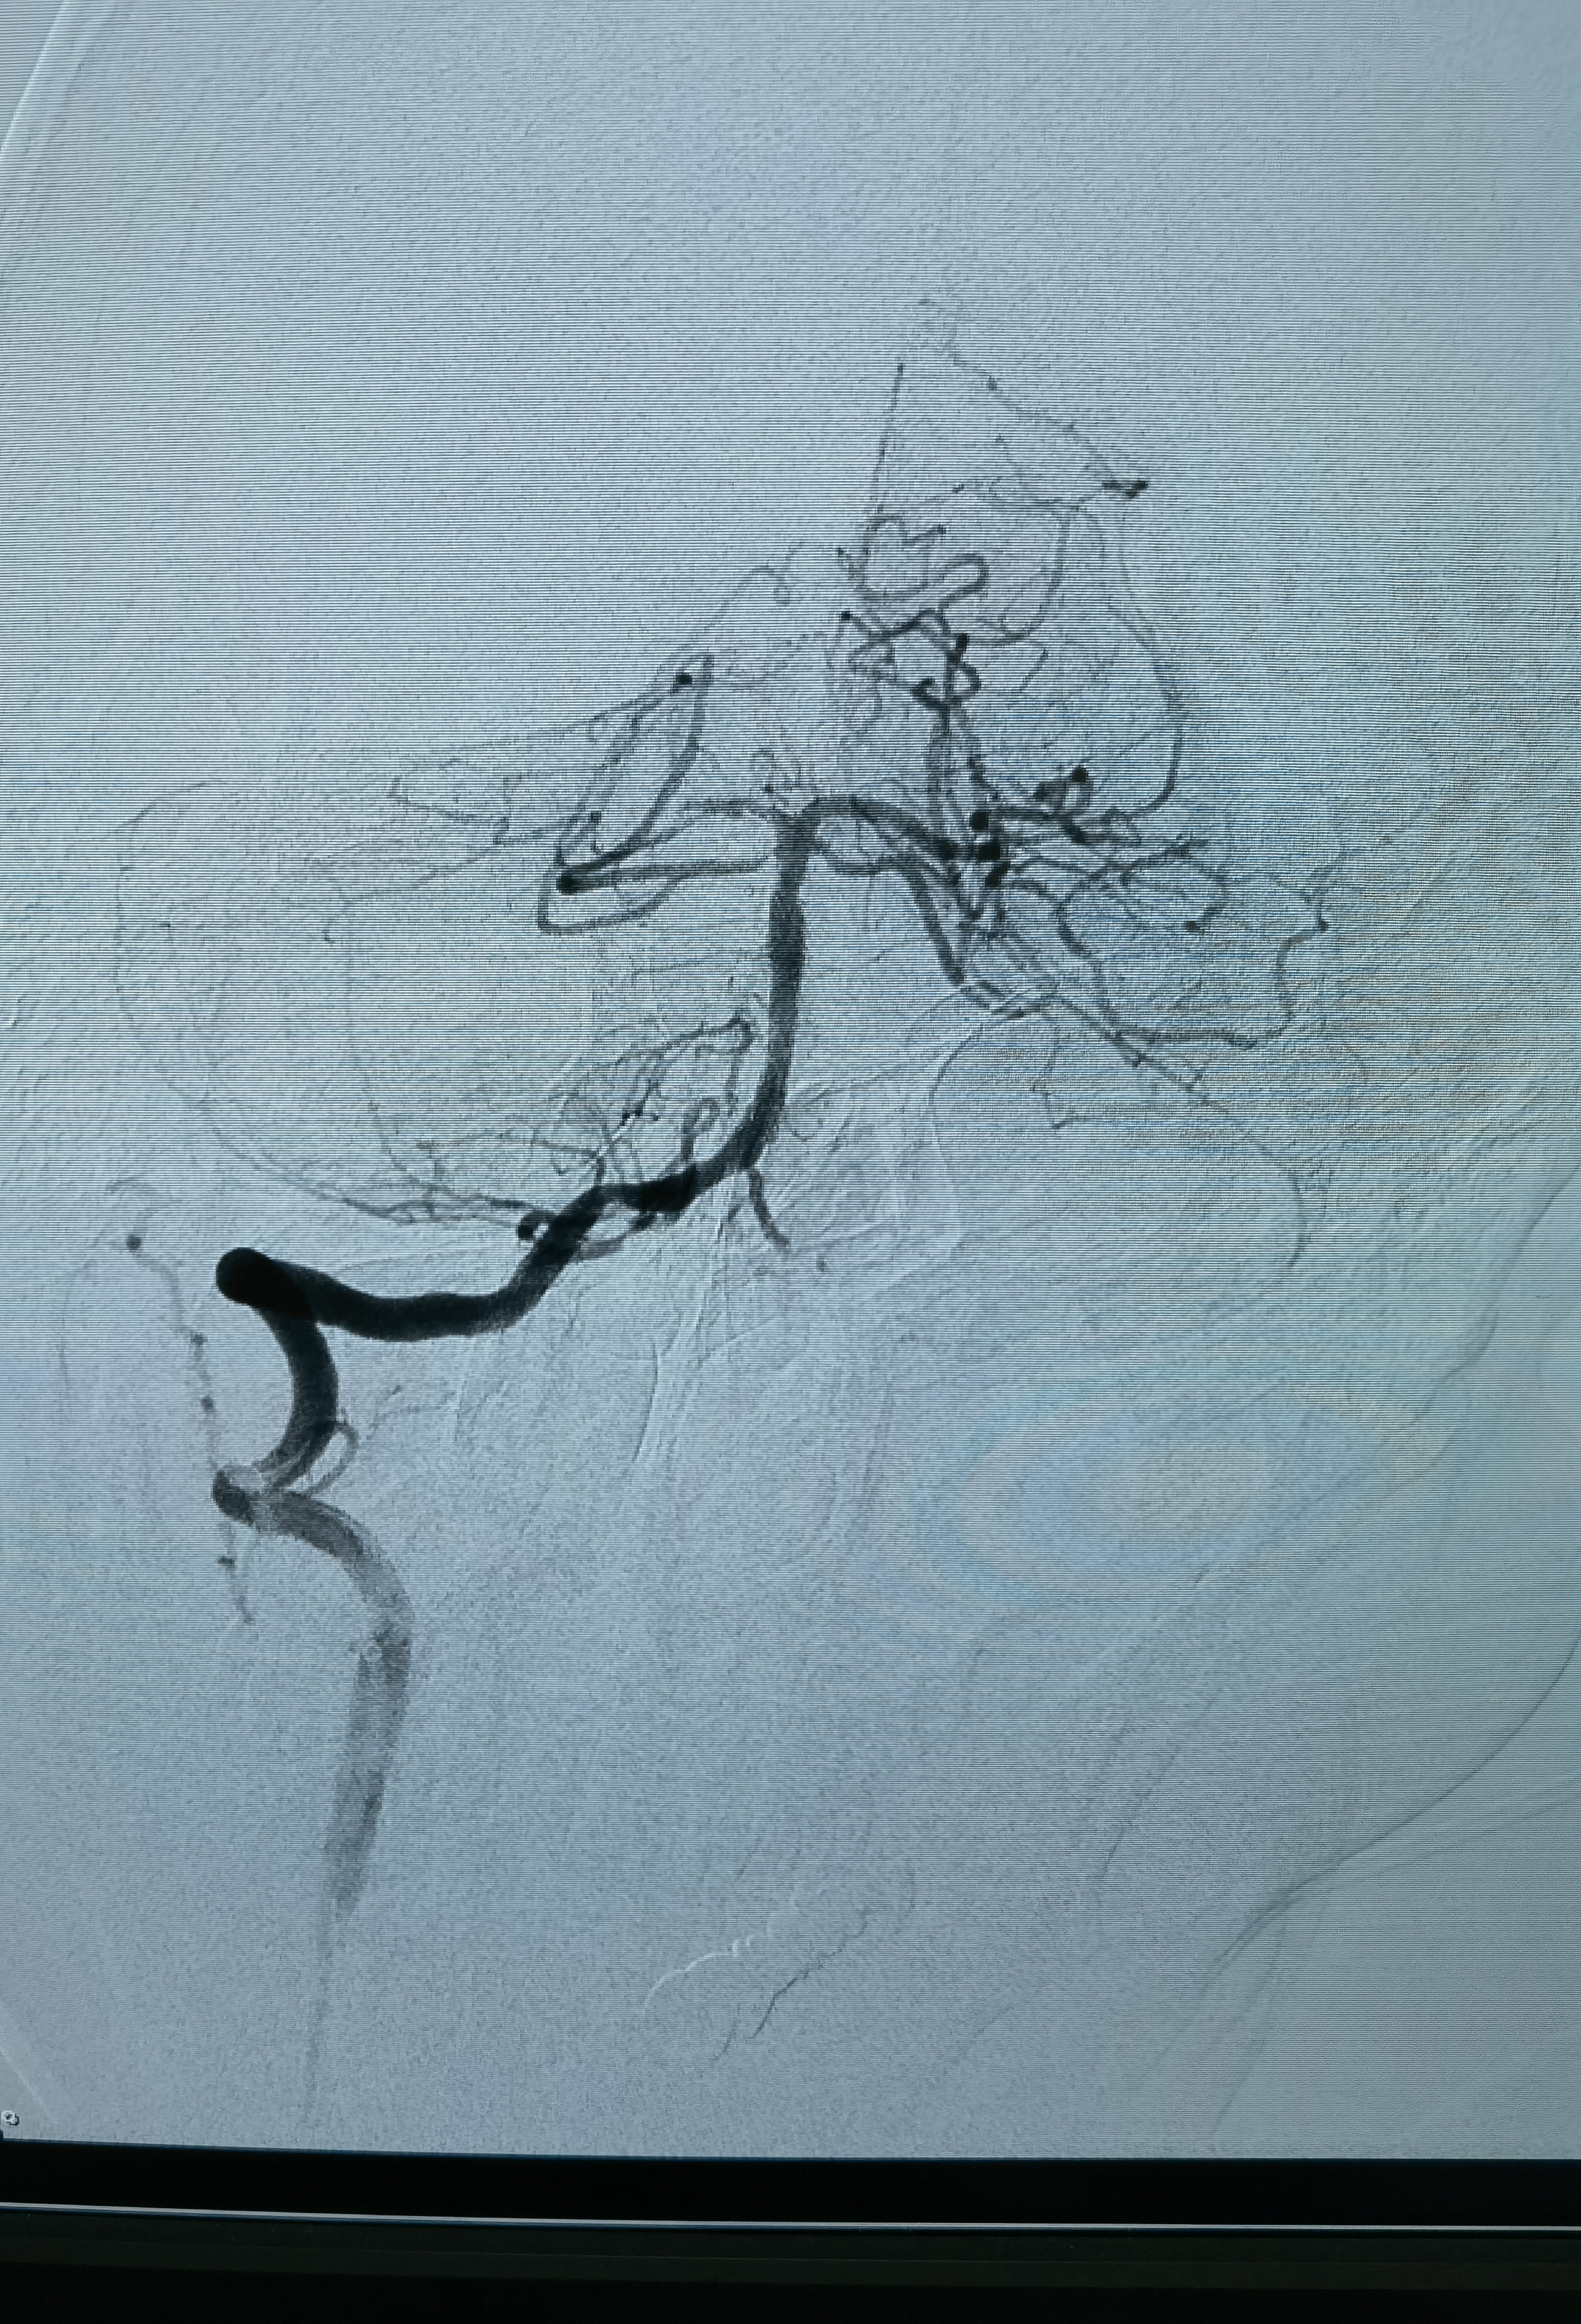

正位造影

侧位造影

工作位造影